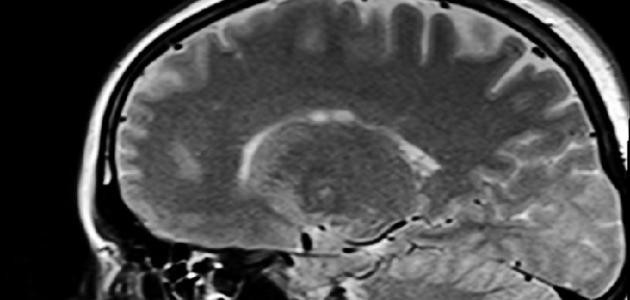

يُعدّ النَزْف داخِلَ المُخّ (بالإنجليزية: (Intracerebral hemorrhage (ICH) نوعاً من أنواع السكتة الدماغية التي تنتج عن نزيف الأوعية الدموية الصغيرة في المخ. ويحدث هذا النوع من النزيف نتيجة ارتفاع ضغط الدم في الشرايين الدقيقة التي تمد الدماغ بالدم، والمغذيات، والأكسجين؛ بحيث يتسبب ارتفاع ضغط الدم بتمزق الجدران الرقيقة لهذه الشرايين مما يؤدي لحدوث نزف داخل الدماغ. ونتيجة لتراكم الدم المتجلط والسوائل يزداد الضغط على الدماغ مما قد يؤدي إلى انضغاط الدماغ أو انفتاقه. ونتيجة تمزق جدران الشريان فإنّ المنطقة التي يغذيها ذلك الشريان تصبح محرومة من الدم الغني بالأكسجين، الأمر الذي يؤدي إلى موت تلك المنطقة وانتفاخ الدماغ. وقد يندفع الدماغ إلى الأسفل نتيجة زيادة الضغط عليه من خلال الفتحة الصغيرة في قاعدة الجمجمة المسماة الثُّقْبَة العُظمى (بالإنجليزية: Foramen magnum)، كما يمكن أن يتم ضغط أجزاء الدماغ التي تتلامس مباشرة مع العظم حول هذا الفتحة بحيث تتوقف عن العمل، ونظراً لأنّ هذه المناطق الدماغية تتحكم في التنفس ومعدل ضربات القلب فقد يؤدي ذلك إلى الموت.

- النزف داخل المخ: (بالإنجليزية: Intracerebral hemorrhage)، يحدث النزف داخل المخ نتيجة وجود نزيف داخل الدماغ، ويُعدّ أكثر أنواع النزيف داخل الرأس شيوعاً. وتُعدّ علامة التحذير البارزة لهذا النوع من النزيف البداية المفاجئة للعجز العصبي.